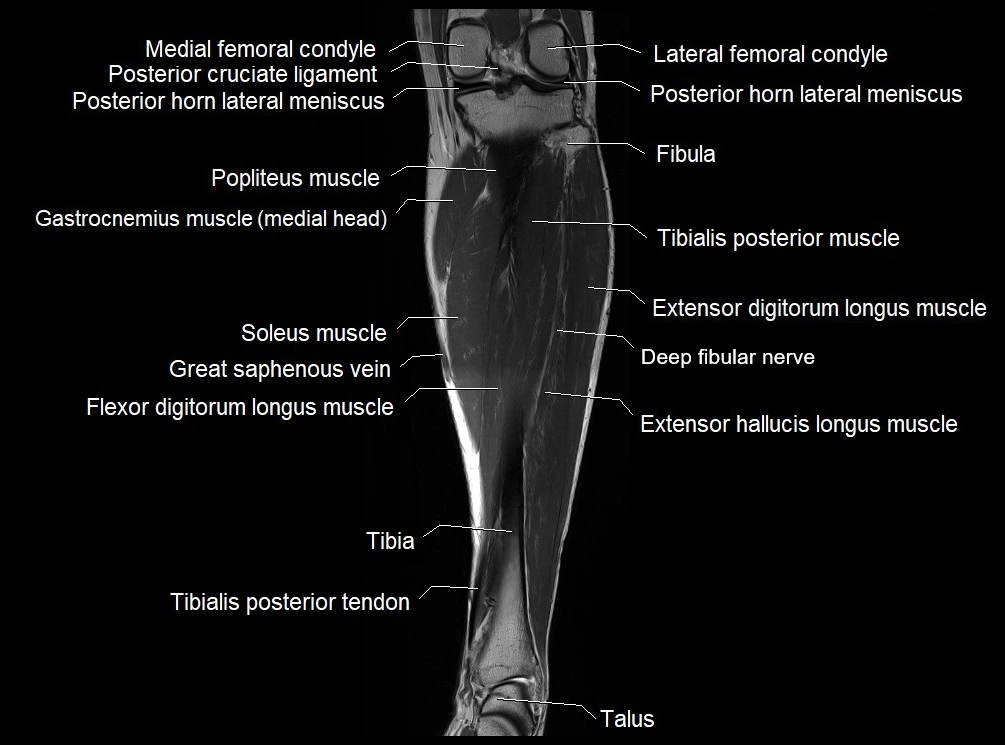

MRI image